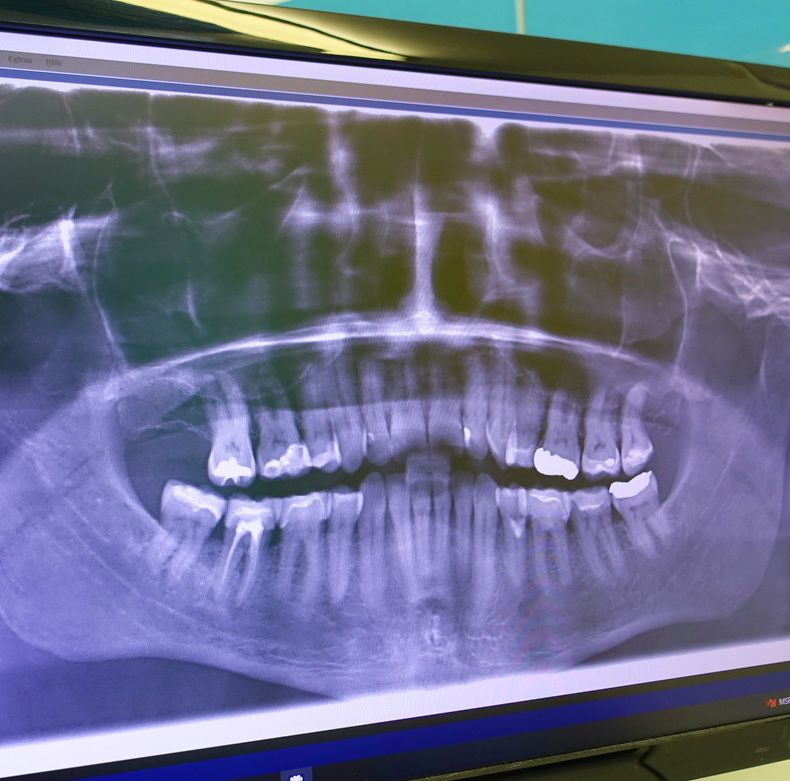

Das digitale Röntgen ist eine moderne bildgebende Technologie in der Zahnmedizin, die es ermöglicht, hochauflösende Röntgenbilder mit reduzierter Strahlenbelastung aufzunehmen. Es ersetzt herkömmliche analoge Röntgensysteme und bietet zahlreiche Vorteile für die Diagnostik und Patientenversorgung.